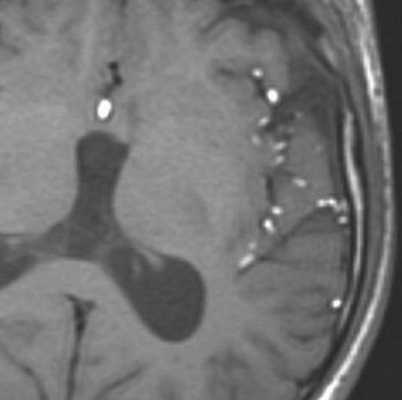

При МРТ головного мозга картина неспецифическая и зависит от содержимого кисты. Если она не содержит жира, топри МРТ головного мозга эпидермоидная киста имеет ликворную интенсивность сигнала. В таком случае эпидермоидная киста трудно отличима от арахноидальной, хотя, как правило, не столь однородная. На FLAIR томограммах и диффузионно-взвешенных МРТ головного мозга содержимое эпидермоидов светлее ликворного. Жировое содержимое, такие эпидермоиды еще называют холестеатомой, приводит к высокому сигналу на Т1-зависимых МРТ головного мозга. Видимо, он обусловлен липидами, но не холестеролом. На Т2-взвешенных МРТ головного мозга он менее интенсивен чем ликвор. Контуры эпидермоидов на МРТ всегда четкие. Холестеатомы составляют всего 3-5% от эпидермоидов. В 15-20% случаев встречается кальцификация по переферии кисты. Редко наблюдается усиление стенок кисты при МРТ головного мозга с контрастированием.

Арахноидальные кисты представляют собой скопление ликвора между листками расщепленной паутинной оболочки. Арахноидальная киста обычно не сопровождается другими мальформациями. Незначительная часть арахноидальных кист имеет приобретенное происхождение - следствие лептоменингита, операции или кровоизлияния. Частота составляет около 1% от внутричерепных образований. Соотношение полов М:Ж, как 4:1. Типичная локализация - средняя черепная ямка (в области Сильвиевой борозды 50%), межполушарная щель, мосто-мозжечковый угол (11%), за скатом или на уровне четверохолмия (10%), в области червя мозжечка (9%), реже в области межножковой и предмостовой цистерн (3%), а также супраселлярной и хиазмальной цистерн. В зависимости от размера предложено делить кисты на 3 типа (Galassi, 2006), что однако, не имеет практического значения. Ретроцеребеллярная арахноидальная киста довольно часто встречаются за мозжечком и отличима от mega cisterna только по неизменённой задней черепной ямке. При МРТ головного мозга содержимое кисты чисто ликворное, стенки гладкие, чётко очерченные, внутри кисты могут быть перегородки. Мелкие арахноидальные кисты очень трудно увидеть при МРТ головного мозга. Меняя ширину окна и его уровень на Т1-зависимых МРТ изображениях можно заметить, что киста чуть светлее ликвора. Дифференциальная диагностика с эпидермальными кистами лучше осуществляется с помощью МРТ последовательности FLAIR. На них при МРТ головного мозга эпидермальные кисты становятся яркими, в отличие от гипоинтенсивных арахноидальных. Вероятно, вариантом арахноидальной кисты является нейроэпителиальная киста, которая при МРТ головного мозга имеет типичное расположение в области хориоидальной щели.

Коллоидная киста - это врождённое нейроэпителиальное образование. Коллоидная киста выстлана эпителием и имеет фиброзную капсулу. Она составляют около 1-2% объемных внутричерепных образований. Обычно диагностируются в возрасте между 30 и 50 годами. Всегда расположена в переднее-верхнем отрезке III желудочка между отверстиями Монро. Контур ее четкий, форма округлая, содержимое бывает неоднородное. Размер от 3 мм до 4 см, при больших размерах она закрывает отверстия Монро и вызывает окклюзионную гидроцефалию. Сигнал зависти от примеси белка к ликвору. При наличии белкового мукоидного содержимого киста гиперинтенсивна на Т1-взвешенных МРТ головного мозга и гипоинтенсивна на Т2-взвешенных МРТ, но встречаются варианты гиперинтенсивные на МРТ головного мозга обоих типов взвешенности кольцевидные или смешанные. При МРТ головного мозга с контрастированием усиления сигнала не наблюдается.